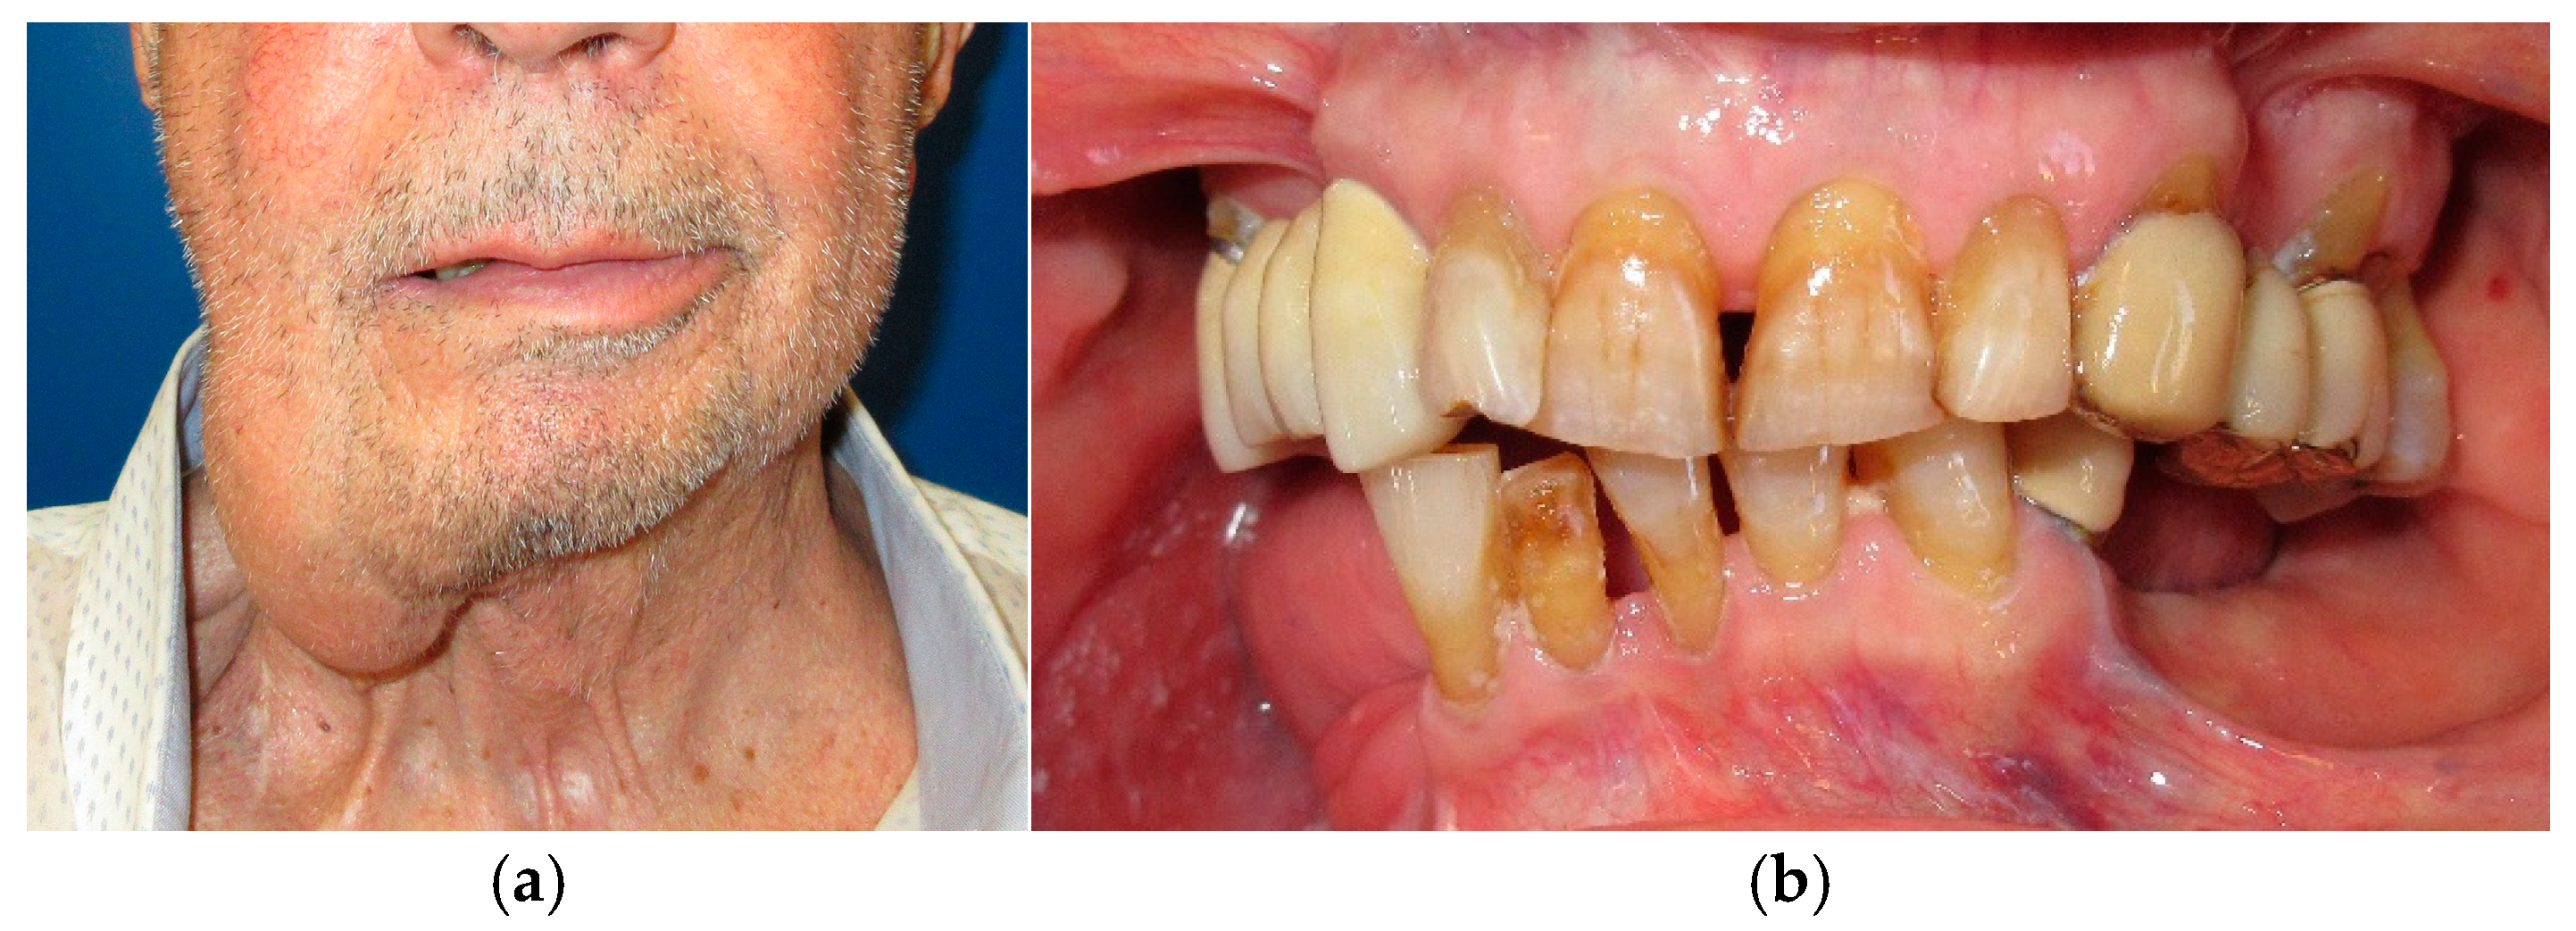

The patient in case n°4 underwent hemimandibulectomy resulting in an extensive bone defect (L1-2-3) that included the conoid process, the angle of the mandible and a portion of the body of the mandible (Figure 13 and Figure 14). Due to the defect, both functional movements of open and closure appear massively deviated: despite the presence of six dental elements (31, 32, and 33 treated endodontically and with a prosthetic crown and 41, 42, and 43), the lack of the coronoid process due to surgical resection does not allow for a more centered position of the mandible, as the surviving segment tends to deviate and pull massively towards the surgical side.

The trajectory of the opening movement presents a further deviation. The deep bite probably represents a worsening factor for the deviation, due to the lack of proprioception (Figure 15).

Figure 13. Patient with hemimandibulectomy L1,2,3 in extra- (a,b) intraoral view.